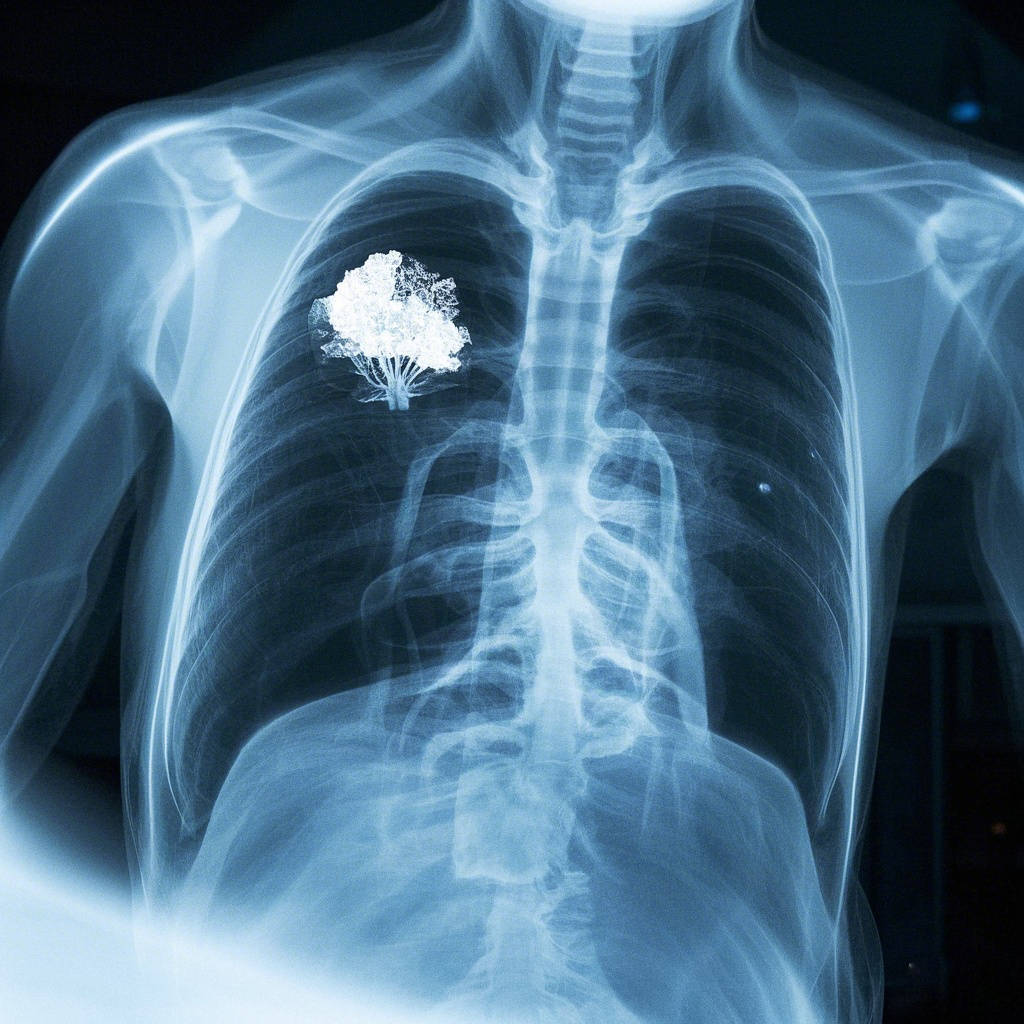

在中医的宝库中,有许多奇妙的配伍组合,为各类疾病的治疗提供了独特思路。对于困扰不少人的肺结节问题,鸡内金搭配一味药,往往能发挥出意想不到的效果。其中,一味药负责健脾渗湿,另一味则专注于化瘀散结,二者协同,共同化解肺结节危机。